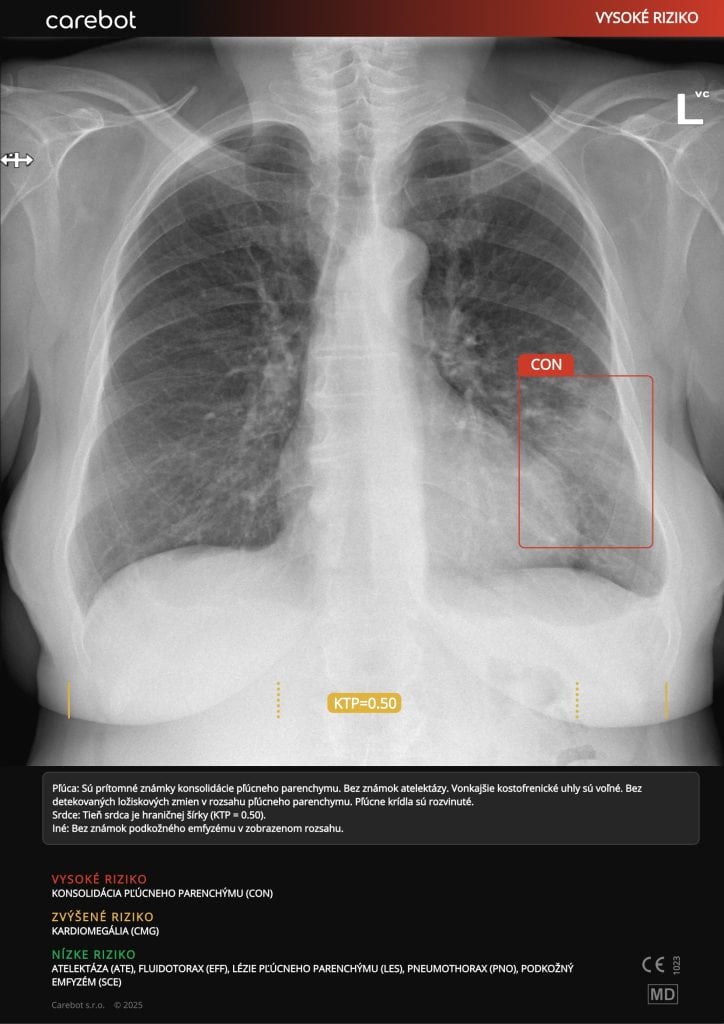

Carebot AI

Skupina AGEL rozširuje využívanie umelej inteligencie Carebot AI na automatickú analýzu röntgenových snímok hrudníka a kostí. Systém dokáže v priebehu niekoľkých sekúnd identifikovať viac než 60 typov nálezov, vrátane zápalov pľúc či zlomenín.

Carebot AI funguje ako „druhý pár očí“ – nehodnotí snímky namiesto lekára, ale upozorňuje na možné patologické oblasti.

Zvyšuje bezpečnosť pacienta, diagnostickú istotu a skracuje čas hodnotenia snímok až o 30 %. Pilotné nasadenie prebieha v Nemocnici AGEL Nový Jičín a ďalších zariadeniach s vysokým objemom vyšetrení. Podľa odborníkov ide o príklad zmysluplnej a praxe overenej implementácie umelej inteligencie v zdravotníctve. Systém je plne integrovaný do nemocničného PACS prostredia, čím odpadá potreba externého softvéru.